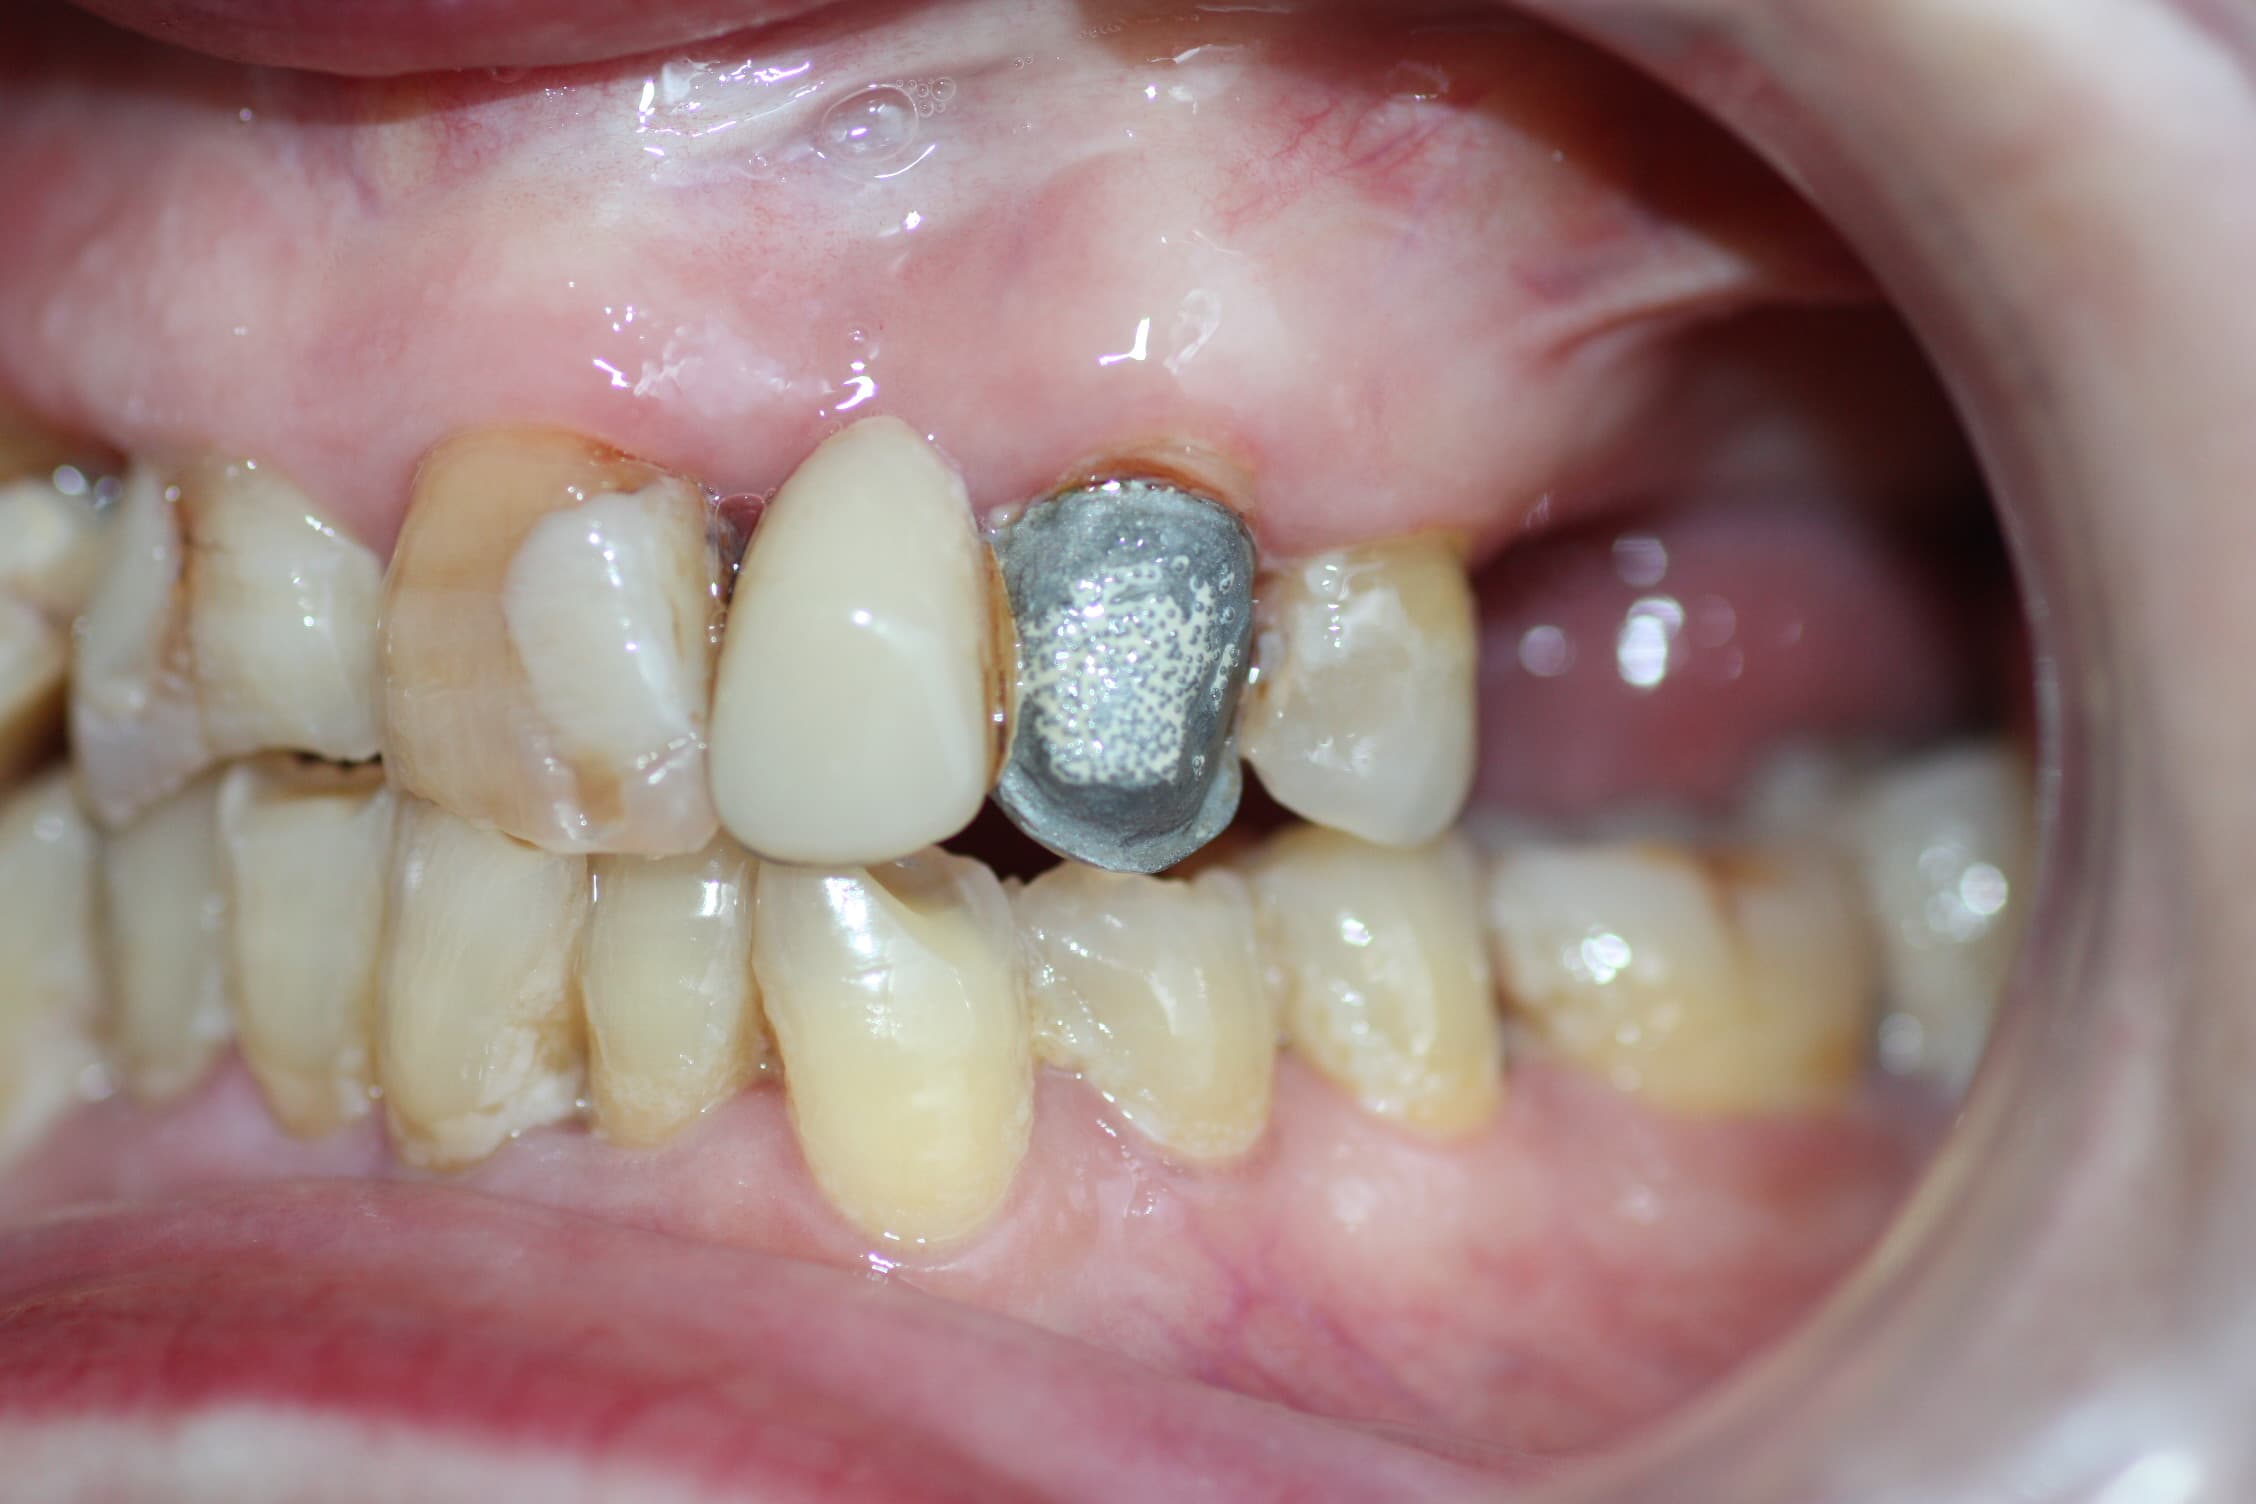

Corona o prótesis caída

Corona dental suelta, prótesis que se cayó o carilla desprendida.